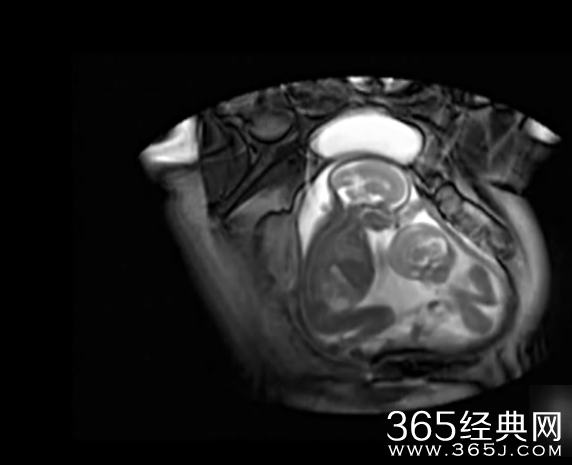

365经典网 左边的姿势舒服,右边的表示抗议,左边是文的嘴在动,右边是武的用脚蹬,这样妈咪真的没反感觉么?大家都看见小的打打的,有没有看见大的让小的呢,不过我看见大的嘴动了吗?